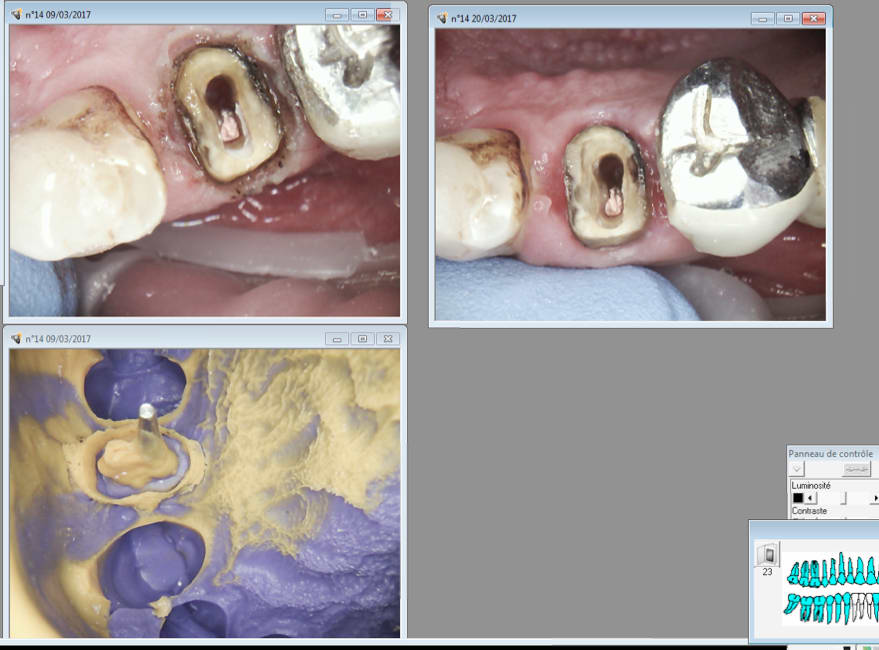

20/03/2017 à 09h54

Celle la ca saignait un peu. -)

Il faudrait que j'arrete de préparer trop sous gingival. Un réflexe à perdre.

Tiens suite de mon Ic à 4 pattes empreinte prise le 9 03 et pose aujourd'hui. Aspect de la gencive encourageant après le coup de laser.